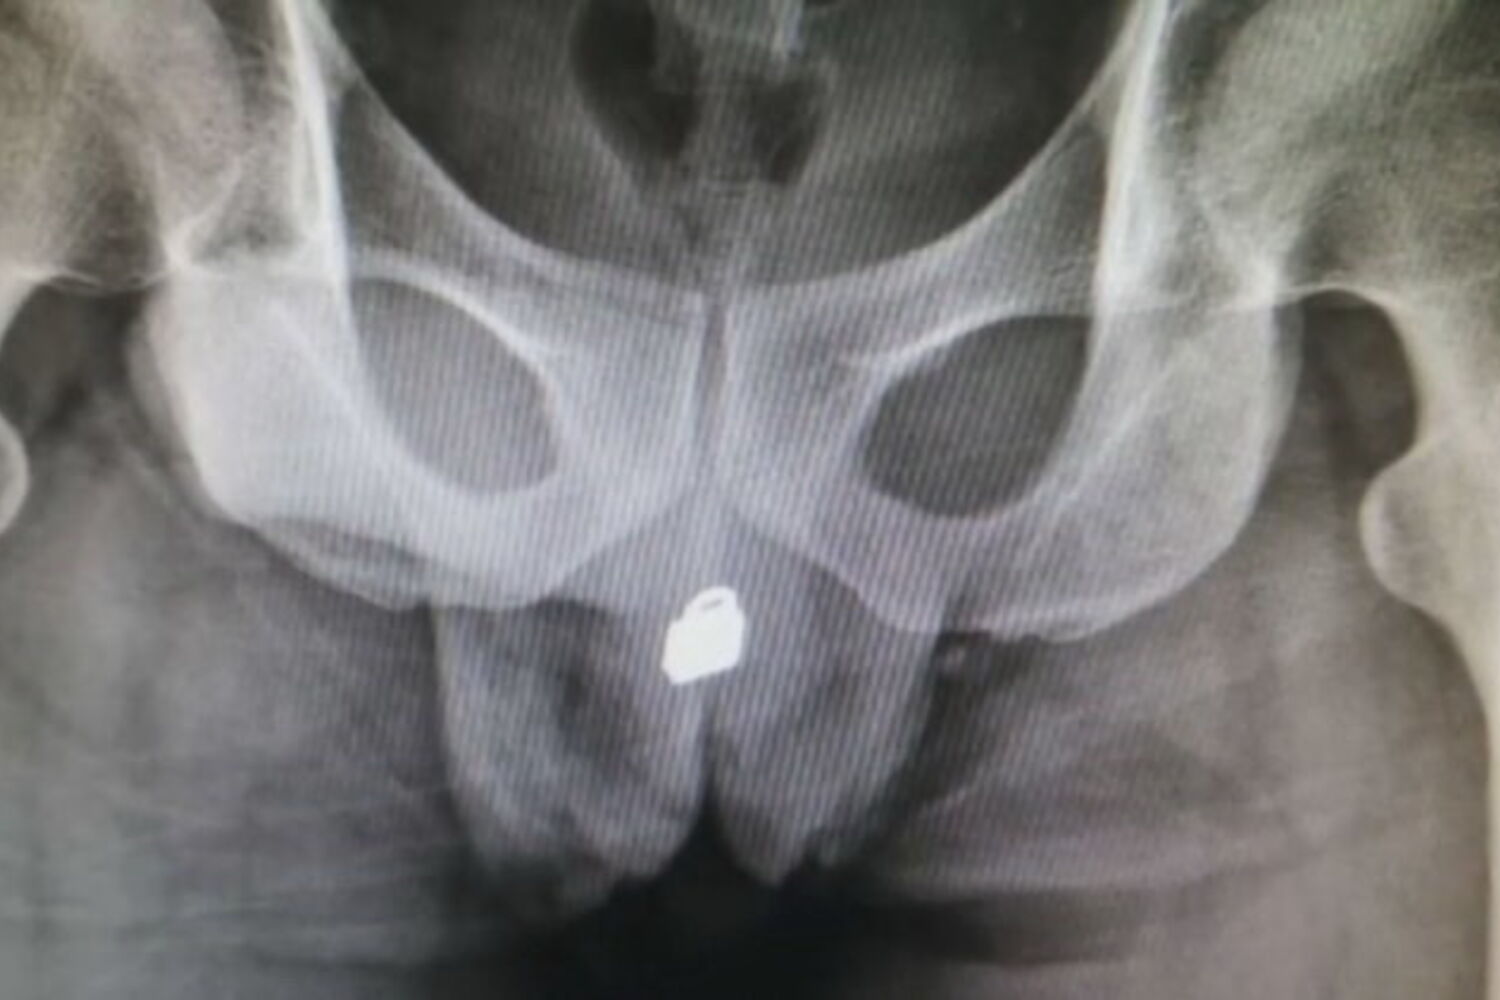

Um homem chinês de 31 anos teve que ser operado de urgência depois de ter dado entrada no hospital com um pequeno cadeado de metal alojado no interior da bexiga.

Aos médicos, o homem (que não quis ser identificado) recusou revelar o que se passava mas, depois de fazer um raio-X, o problema ficou à vista. Acabou por revelar que tinha inserido o pequeno objeto metálico na uretra e que depois o empurrou para dentro do pénis para ter prazer sexual.

O cadeado de pequenas dimensões acabou por entrar na bexiga e causar um bloqueio e muitas dores ao homem.

Foram feitos vários testes até se decidir se era ou não seguro operar o paciente e a cirurgia implicou extremo cuidado.

Os médicos acabaram por conseguir retirar o cadeado depois de fazerem uma incisão na bexiga. O homem continua internado e deverá ficar com sequelas permanentes no aparelho urinário.